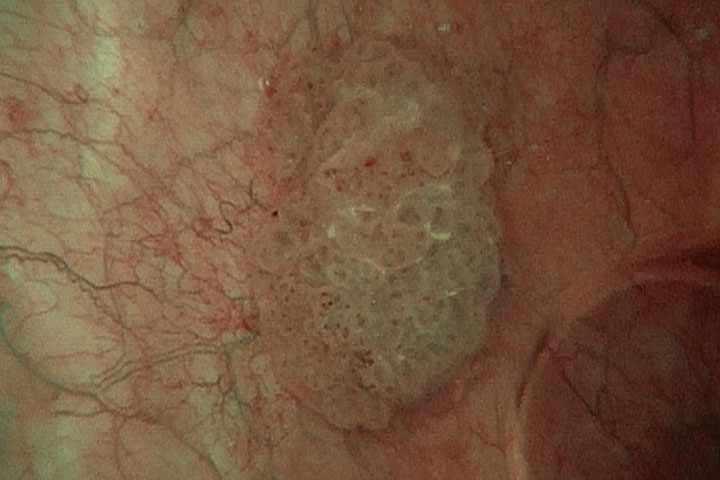

Патологический рост сосудов вокруг плоской опухоли

— В стандартном «белом» цвете уролог видит картинку, которую дают лучи, отраженные от поверхности слизистой. NBI-система позволяет во время процедуры выделять лучи, отраженные от более глубоких слоев, и видеть патологических ход сосудов, новообразования в более глубоких слоях. К примеру, раковая опухоль — ткань жадная, тянет на себя сосуды, чтобы обеспечить повышенное кровообращение. Самой опухоли еще нет, но врача насторожит повышенное сосредоточие сосудов. Он может тут же взять материал для исследования и, если это предположение подтвердится, сразу же начать терапию. Проще говоря, современный цистоскоп может диагностировать то, что через некоторое время вырастет на поверхности, значит, у врача появляется фора для эффективного лечения.